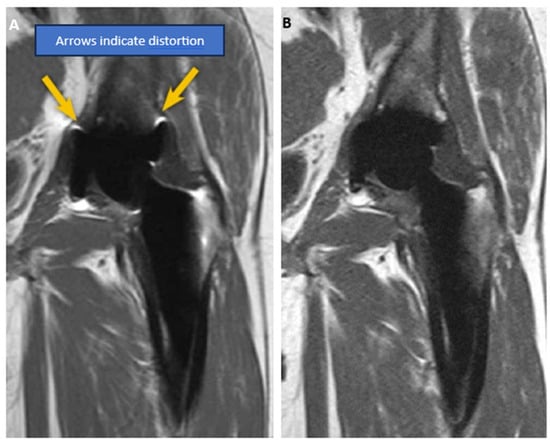

- Software for Metal Implant Imaging. 2019. Available online: https://www.radnet.com/community-radiology/news/software-metal-implant-imaging (accessed on 20 January 2024).